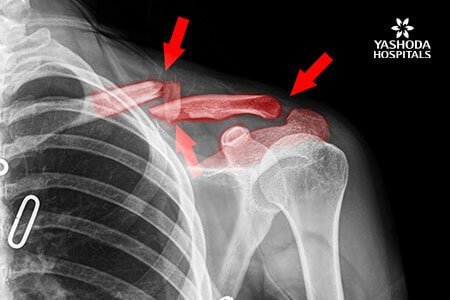

What are the symptoms of Broken Collarbone?

Symptoms of this condition may include one or more of the following:

- Pain usually increases with movement

- Swelling, tenderness, bruising in the affected area

- Bulge near the shoulder

- Grinding or tackling sound when moving the shoulder

- Stiffness or inability to move the shoulder